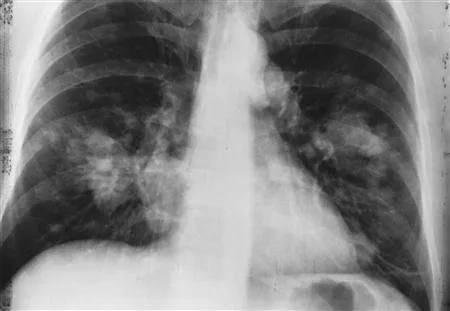

وأفادت الدراسة الجديدة التي نشرت بمجلة «العلاج المناعي للسرطان» بأن «سرطان الرئة أحد أكثر أنواع السرطان شيوعًا في جميع أنحاء العالم وهو السبب الرئيسي للوفيات المرتبطة بالسرطان، غالبا ما يتم تشخيصه في مرحلة متقدمة عندما تكون العلاجات التقليدية أقل فعالية. من أجل ذلك، قام باحثون من جامعة إدنبره بالتحقيق في سبب فشل العلاج المناعي في كثير من الأحيان من خلال فحص الجزيئات التي يمكن أن تتداخل مع نشاط الخلايا التائية؛ وهي نوع من خلايا الدم البيضاء التي تحارب المرض. حيث تعمل العلاجات المناعية من خلال تعزيز نشاط الخلايا التائية السامة للخلايا، والتي تلعب دورًا رئيسيًا في القيام بدوريات في الجسم لاكتشاف الخلايا السرطانية وقتلها، ولكنها غالبًا ما تصبح منهكة عند محاربة الأورام. ومع نمو الأورام، فإنها تستخدم آليات معقدة للهروب من التدمير، بما في ذلك التدخل بنشاط الخلايا المناعية، مثل الخلايا التائية».

وفي هذا الاطار، قام فريق الدراسة بفحص أنسجة الورم من 162 مريضًا يخضعون لعملية جراحية لسرطان الرئة ذي الخلايا غير الصغيرة (NSCLC)، وهو النوع الأكثر شيوعًا، والذي يمثل أكثر من 80 % من حالات سرطان الرئة.